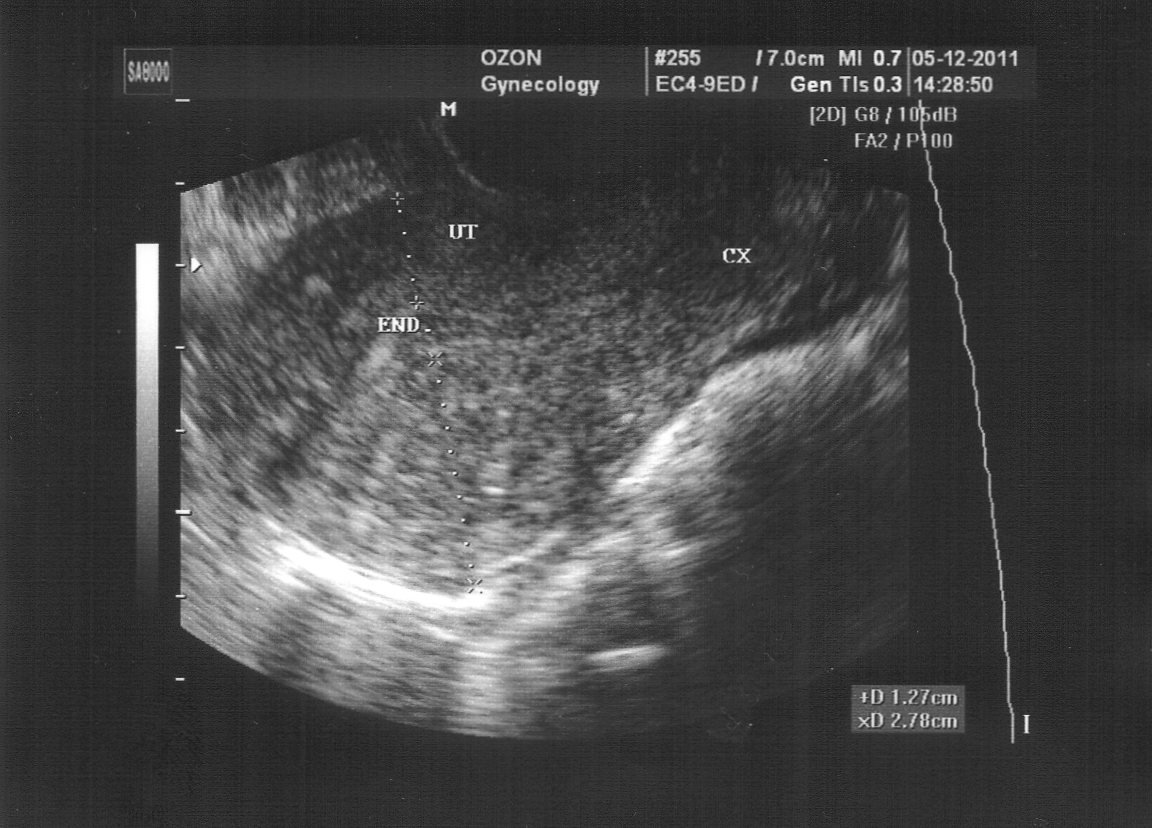

Ультразвуковое исследование (УЗИ) матки

УЗИ проводится на 5–7-й день менструального цикла, когда закачивается бо́льшая часть выделений. Пациентка раздевается и ложится на кушетку, согнув ноги в коленных суставах. В большинстве случаев исследование осуществляется с помощью введения во влагалище специального датчика. Если имеются какие-либо противопоказания к этому способу (девственность, заболевания наружных половых органов), можно проводить процедуру трансабдоминально — через переднюю стенку живота.

Помните, что начальные стадии аденомиоза матки при ультразвуковой диагностике обнаружить практически невозможно.

К основным признакам внутреннего эндометриоза на УЗИ относят:

- изменение формы матки и увеличение её размеров;

- неоднородную структуру миометрия с патологическими включениями;

- утолщение стенки органа;

- отсутствие чёткой границы между эндометрием и мышечным слоем.

На снимке можно заметить неоднородность мышечной ткани из-за включений эндометрия